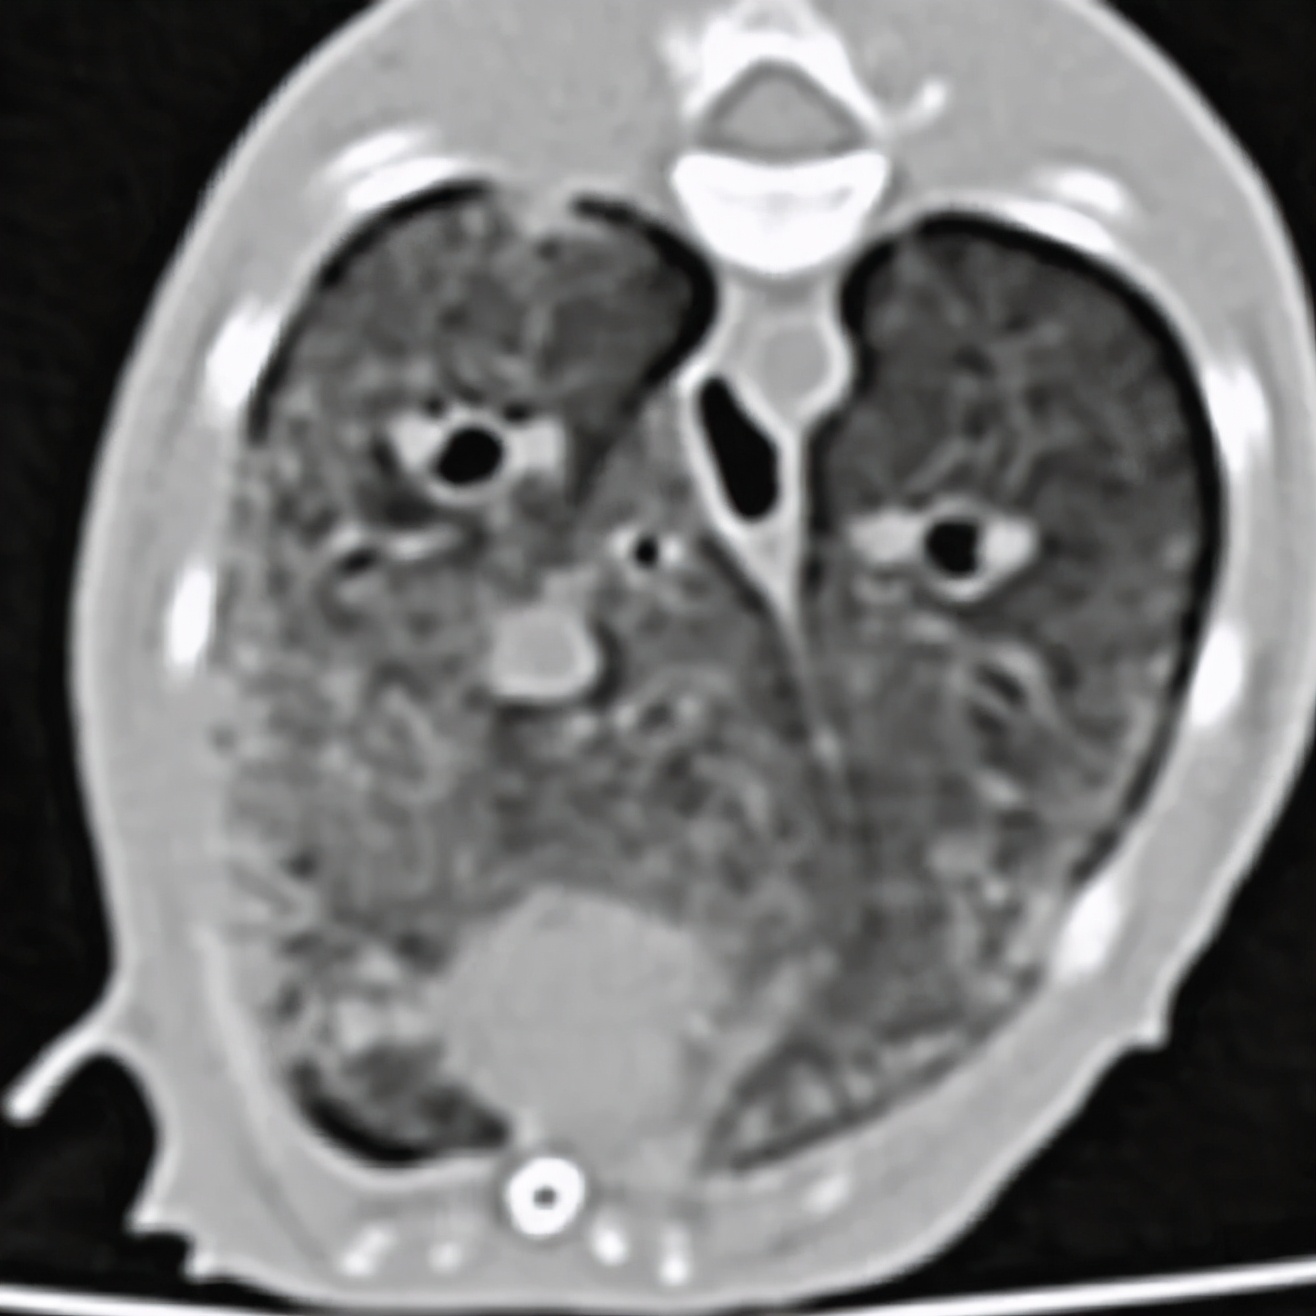

疱疹病毒等检测隐形,抗生素治疗不敏感,血液检查发现高钙血症,CT显示主动脉弓、主动脉根部矿化,肺部表现与矿化、纤维化或炎症表现一致。

经详细病史排查及第三方机构检测,发现主人饲喂的罐装零食存在维生素过量,诊断为高维生素D中毒。